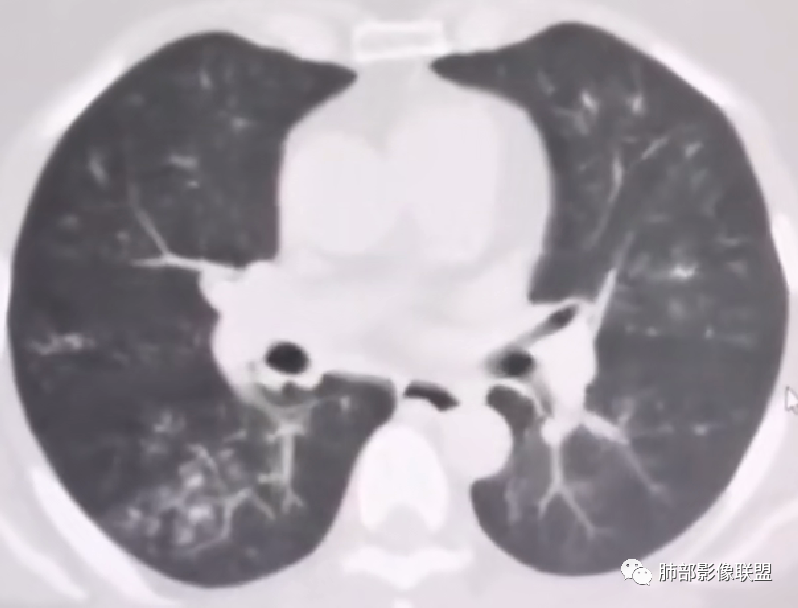

支气管壁增厚、毛糙,考虑气道侵袭性曲霉。

病史+支气管壁增厚+支气管肺炎影像病理基础的苏联红色革命+气喘=气道侵袭性曲霉

弥漫性支气管壁增厚,结合气管镜及痰鸣音,考虑气道曲霉

慢性病程,双肺支气管管壁增厚,周围可见多发点片状高密度影,边缘模糊不清,考虑气道侵袭性曲霉菌病

两肺支气管管壁增厚,沿支气管斑点状及斑片状高密度影,边缘模糊,考虑气道侵袭性曲霉菌,鉴别金葡萄、铜绿

居住地长年潮湿,老年女性,两肺支气管管壁增厚明显,考虑气道侵袭性曲霉菌,鉴别结核。

沿支气管血管束走形,气道壁增厚,边缘模糊,考虑考虑气道侵袭性曲霉,鉴别淋巴瘤。

中老年女性,气道分布的病变,有树芽树雾征,有支气管粘液栓,还有支气管壁增厚,考虑感染性病变,ABBA可能性大,鉴别支原体及军团,支原体以小孩多见,症状轻影像重,发病年龄及影像都不符合,患者住一楼,开麻将馆有聚集性,场地潮湿,不能排除军团肺炎!综合考虑ABBA,不排除军团

1.病灶沿支气管分布的特点相当明显,相应支气管壁广泛增厚。这种与支气管关系极为密切的片影和/或结节影,常高度提示气道相关感染,如支气管肺炎。

3.支气管壁广泛增厚对气道侵袭性曲霉病具有一定的提示意义。注意患者没有支气管扩张,临床也未提供IGE等实验室资料。

一,气道侵袭性曲霉病(PNTA)

1.器官支气管管套样壁增厚和/或支气管扩张,注意壁增厚较均匀,和/或伴有播散性小片影及结节影,注意这些小片影或结节影边界有时较普通炎性病灶清楚。